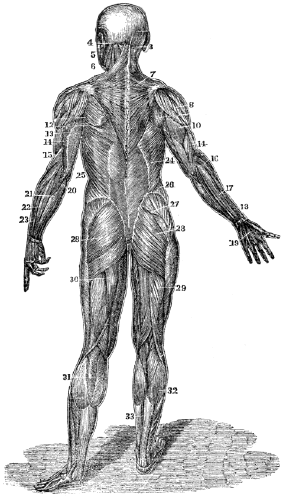

Fig. 2.

Fig. 2. Represents a portion of broken muscular fibre of animal life, (magnified about seven hundred diameters.)